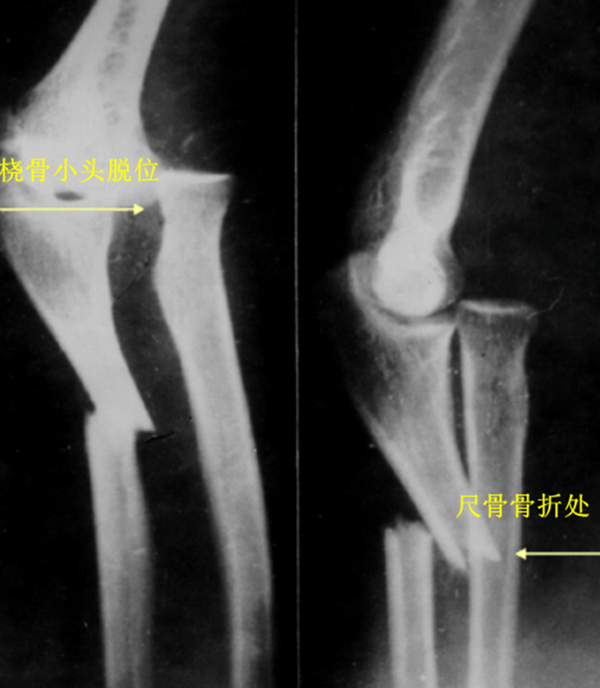

新鲜孟氏骨折的X线片评估内容必须包括标准尺桡骨正侧位片,摄片范围包括腕关节和肘关节。正常情况下,无论肘关节屈伸角度如何,经过桡骨颈和桡骨头中心的线应该通过肱骨小头的中心。

诊断

多以局部肿胀、疼痛为主;移位明显者前臂背侧可见尺骨成角畸形。伴有前臂旋转功能和肘关节活动功能障碍。